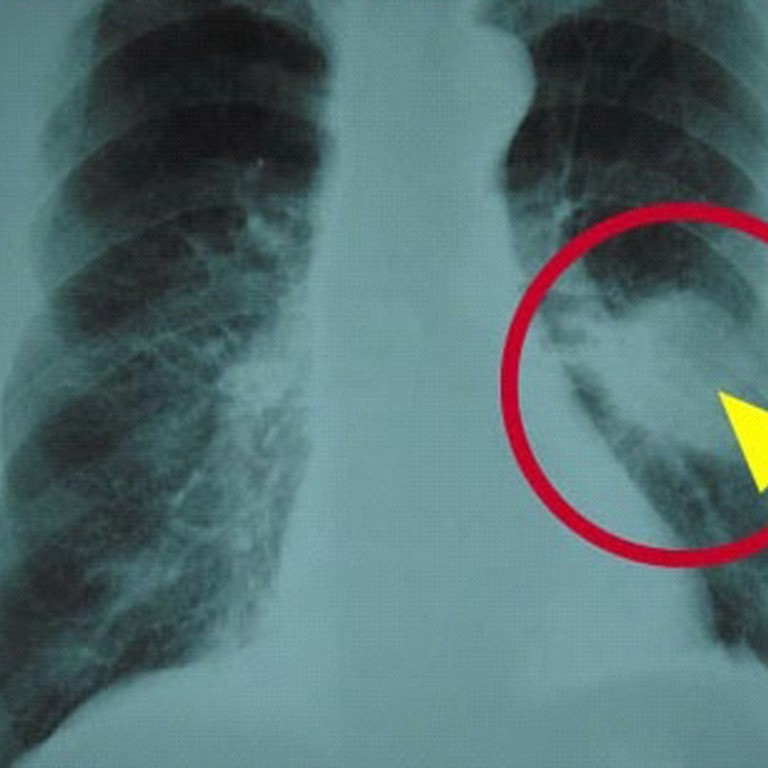

Genetic testing for risk of lung cancer: Some lung cancers, such as non small cell lung cancer have changes in particular genes and proteins. How is genetic testing done?

Describe how targetable mutation genes interrelate with the genes identified as variants of unknown significance; Gene tests can also help your doctor find the right treatment for you if you do get lung cancer. Doctors may use genetic testing to diagnose and treat lung cancer.

Genes are found on chromosomes within all cells. These tests can identify specific genetic changes in the tumor cells that might be treatable with targeted therapies. Among the three main histologic subtypes of nsclc, lung adenocarcinoma (luad) is the most common, followed by lung squamous cell carcinoma (lusc) and large cell carcinoma ().besides having different histologic bases, these subtypes have disparate clinical presentations and unique genetic profiles ().